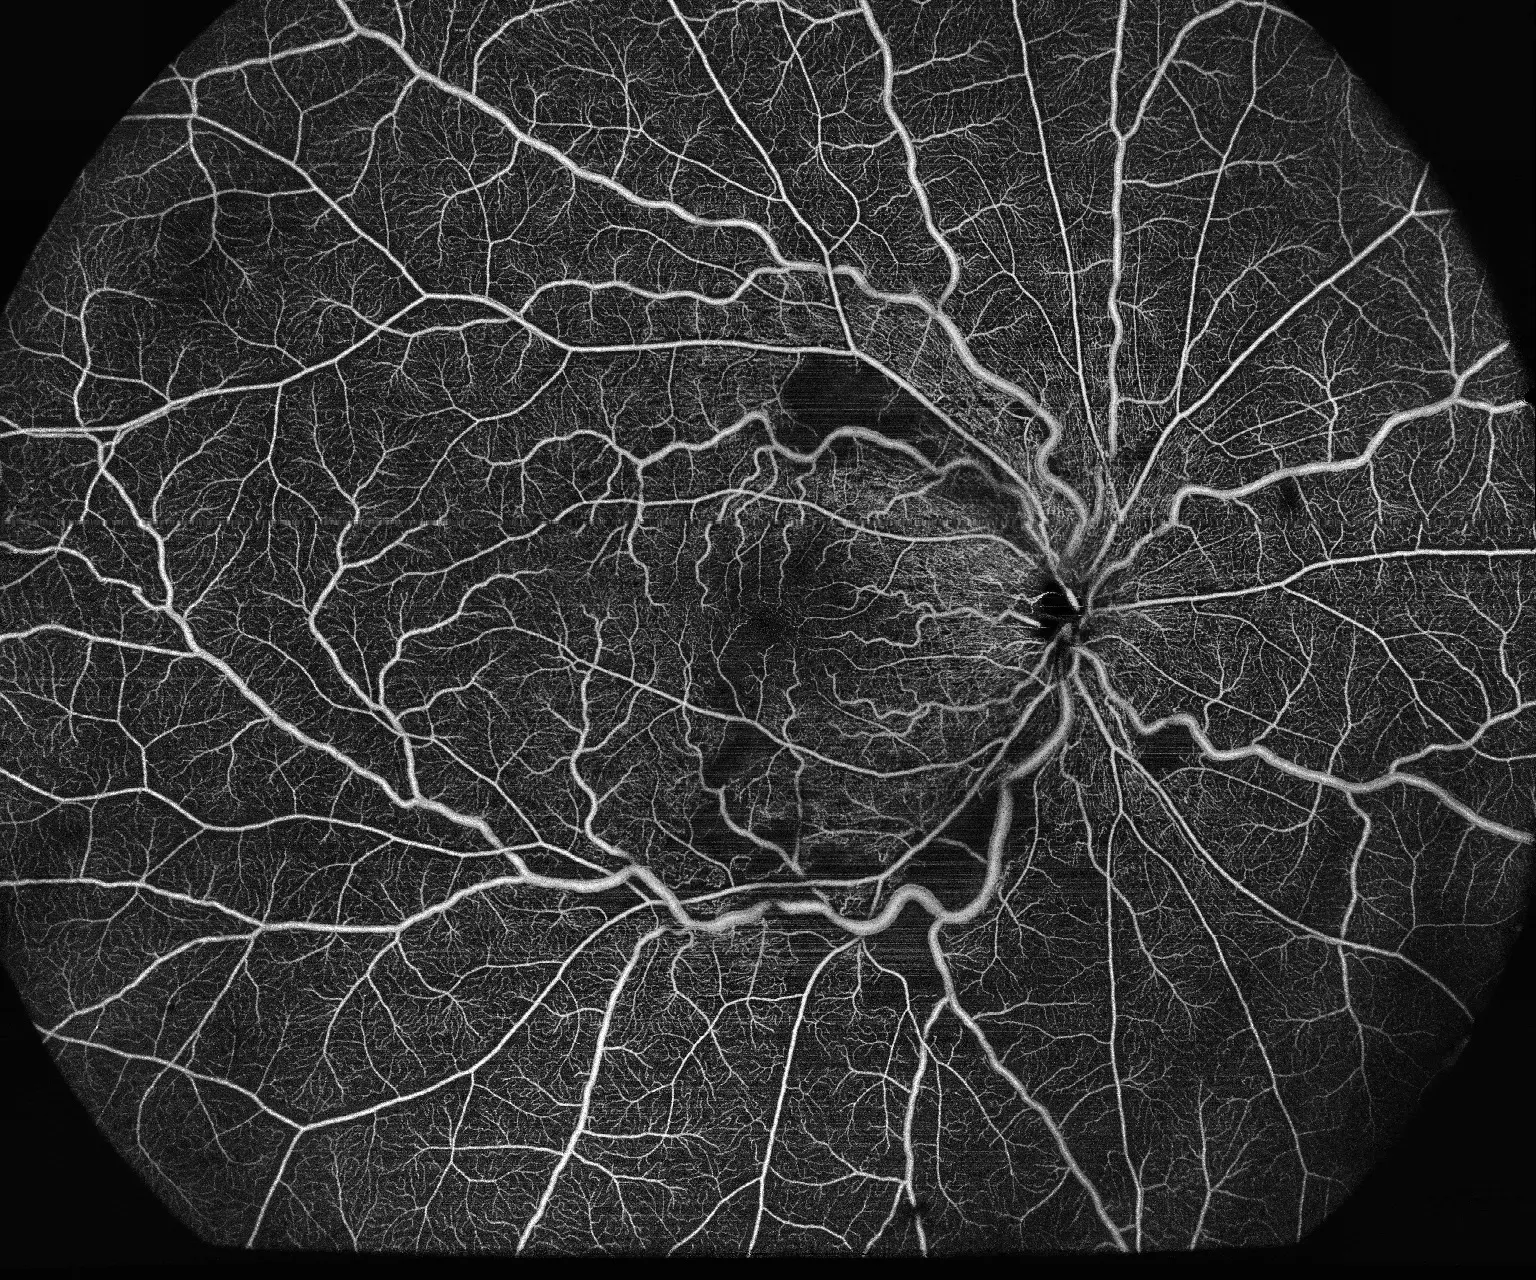

Umożliwia obrazowanie OCTA w zakresie 24×20mm, co pozwala na wykrywanie patologii obwodowych siatkówki, wcześniej niedostępnych dla standardowych systemów.

Ultra-szerokokątne obrazowanie 24×20mm wykrywa zmiany obwodowe siatkówki

BMizar umożliwia diagnostykę patologii w obszarach siatkówki niedostępnych dla standardowych systemów OCT. Dzięki rekordowemu polu widzenia placówka może wykrywać wczesne stadia retinopatii cukrzycowej, obszary niedokrwienia i neowaskularyzację obwodową, co przekłada się na lepsze wyniki leczenia pacjentów i buduje reputację ośrodka jako centrum diagnostycznego najwyższej klasy.

Maks. rozdzielczość (pojedynczy skan)

1536×1280

Ultra-szerokokątne obrazowanie 24×20 mm umożliwia wykrywanie zmian obwodowych siatkówki niedostępnych dla standardowych systemów OCT